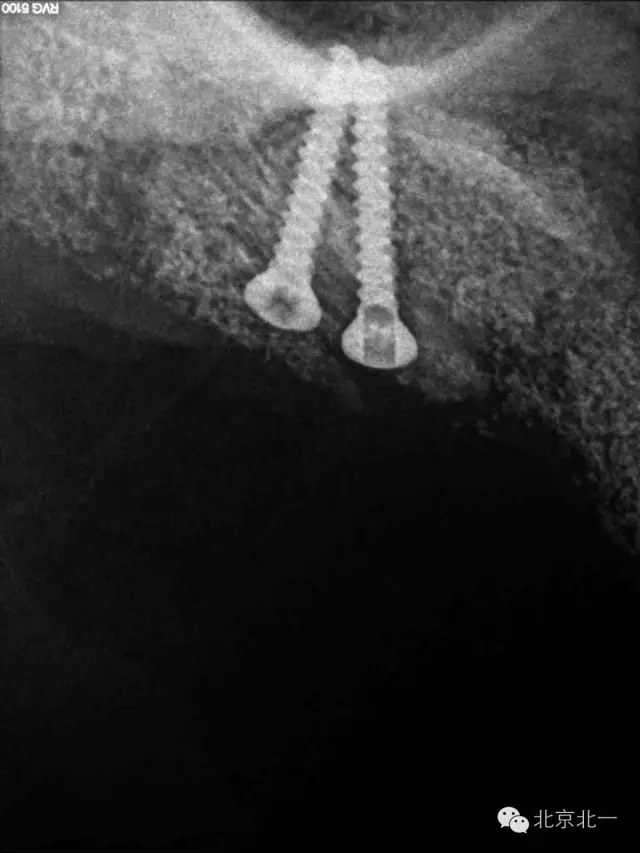

圖十二:切開取出螺釘。

圖十三:取出螺釘。

圖十四:螺釘

圖十五:備洞